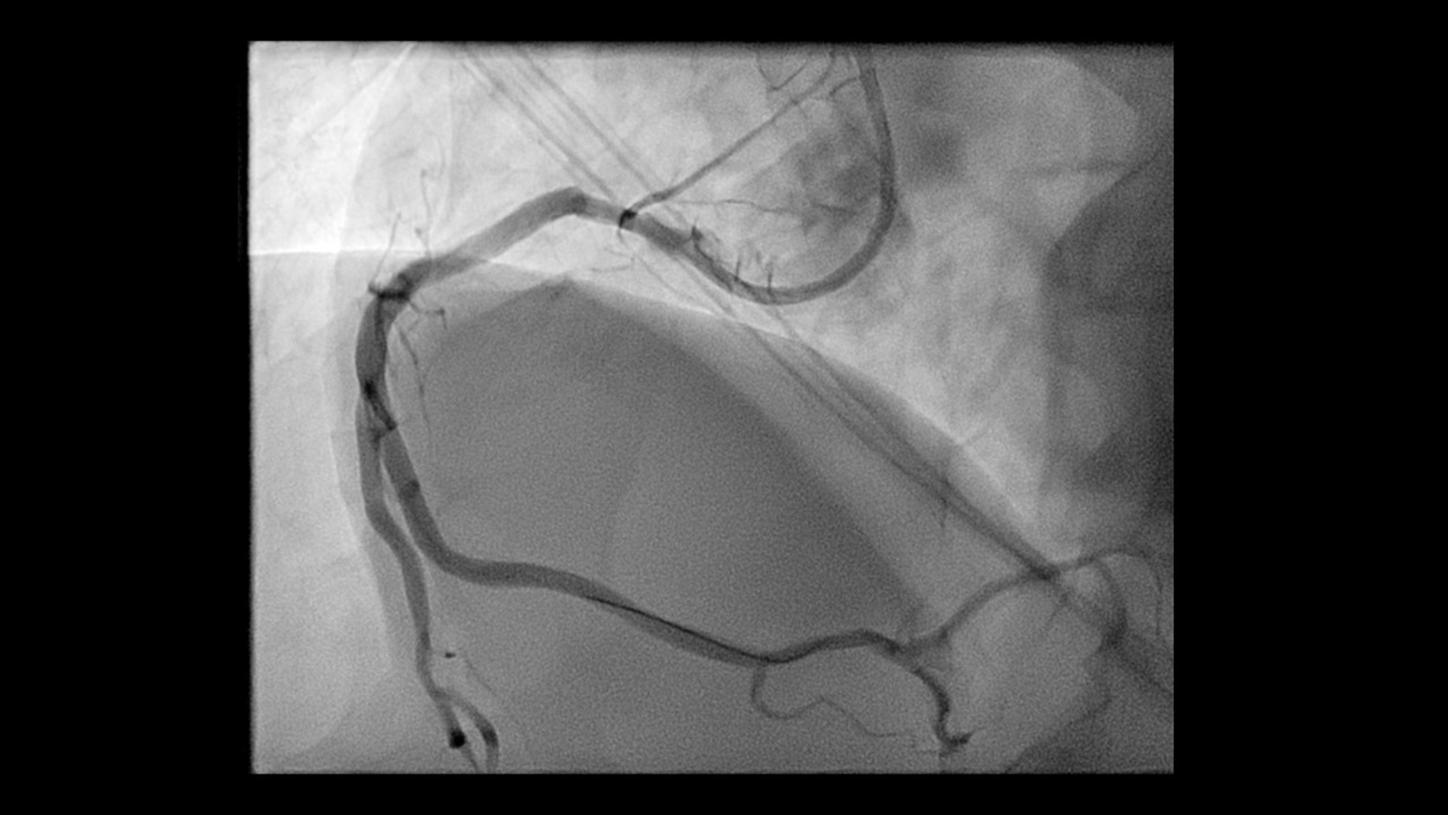

During minimally invasive procedures, it is critical to have a clear view of anatomies and devices. Yet complex imaging tasks or challenging patient conditions often impact image quality. OPTIQ AI delivers constant image quality1 defined by CNR in support of the ALARA principle, independent of patient or C-arm angulation. On top, an AI-powered algorithm reduces image noise in real time across different 2D imaging modes.

Make AI-powered imaging and clear insights your standard during interventions – with OPTIQ AI.